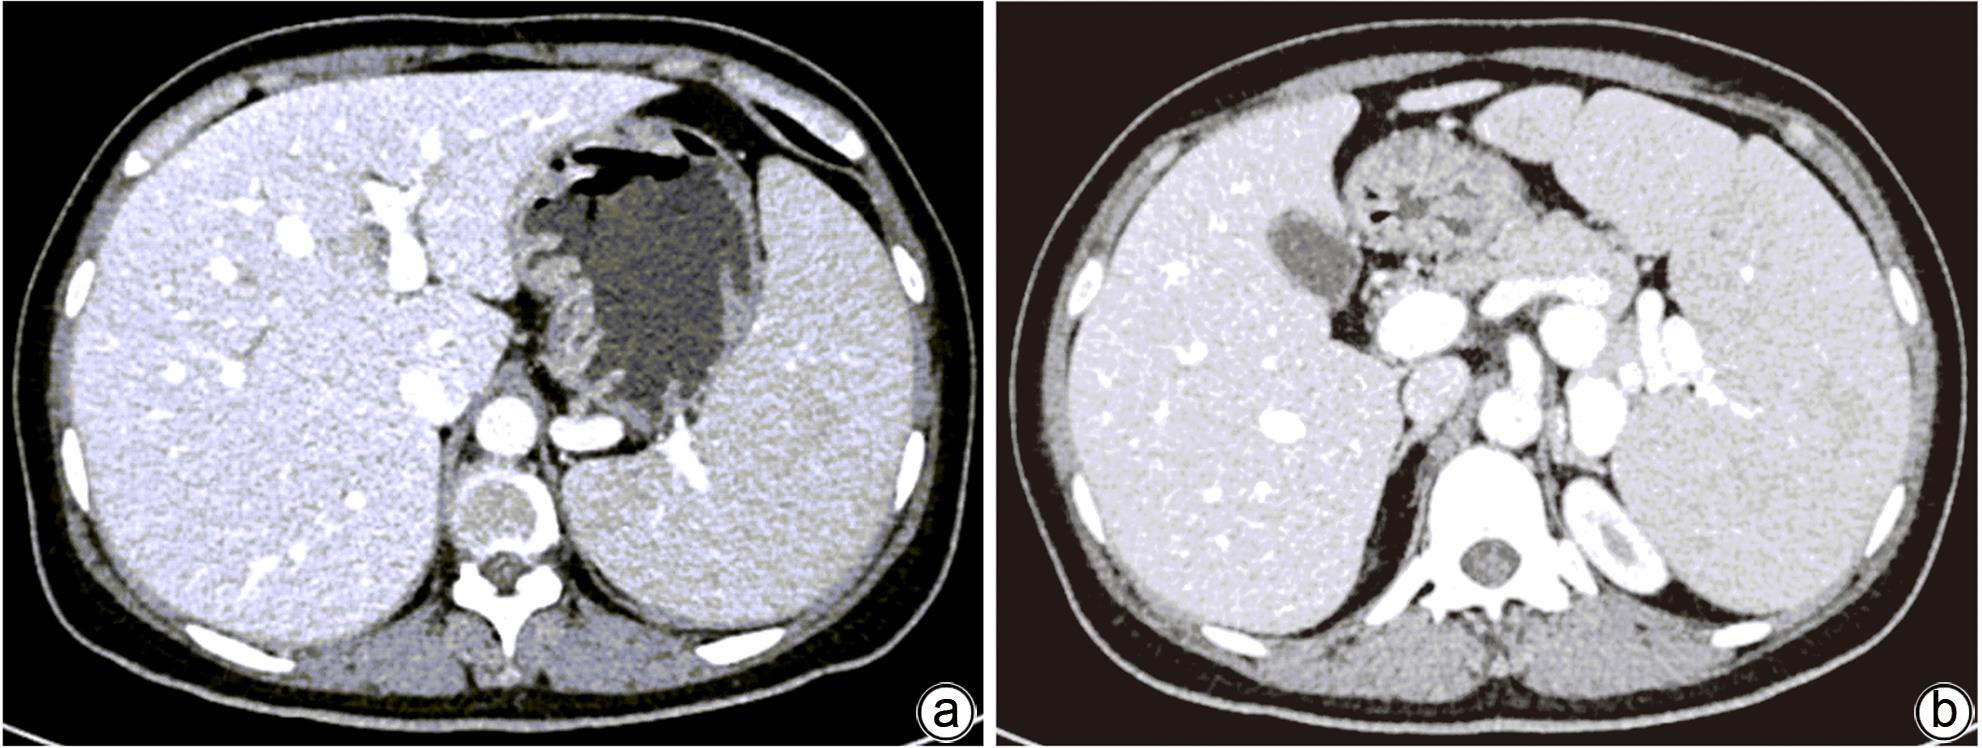

B型尼曼-皮克病及其肝脏受累的异质性表现1例报告

2024, 40(2): 356-360. DOI: 10.12449/JCH240221

摘要(1039) HTML (369) PDF (1123KB)(117)

摘要:

本文报道以“肝脾肿大待查”为主诉,经各项检查确诊为B型尼曼-皮克病的案例,并通过文献复习,总结B型尼曼-皮克病肝脏受累的异质性表现,旨在提高疑难罕见肝脏疾病的临床诊治水平。